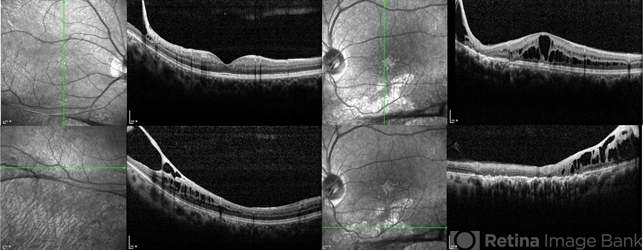

- Xlinked juvenile retinoschisis

- foveal schisis, juvenile retinoschisis, inferotemporal retinoschisis

- Optical coherence tomograph of a 27-year-old male with x-linked juvenile retinoschisis shows foveal retinoshisis in his left eye and inferior inner retinal schisis in both eyes.